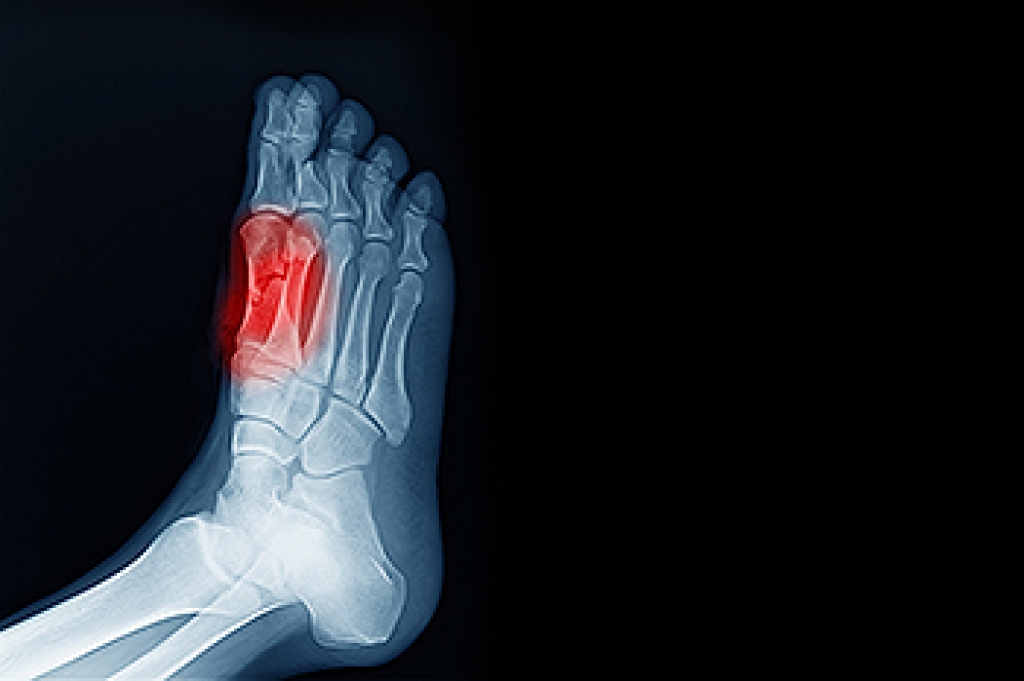

Due to the wide variety of potential causes of ankle pain, podiatrists will utilize a number of different methods to properly diagnose ankle pain. This can include asking for personal and family medical histories and of any recent injuries. Further diagnosis may include sensation tests, a physical examination, and potentially x-rays or other imaging tests.